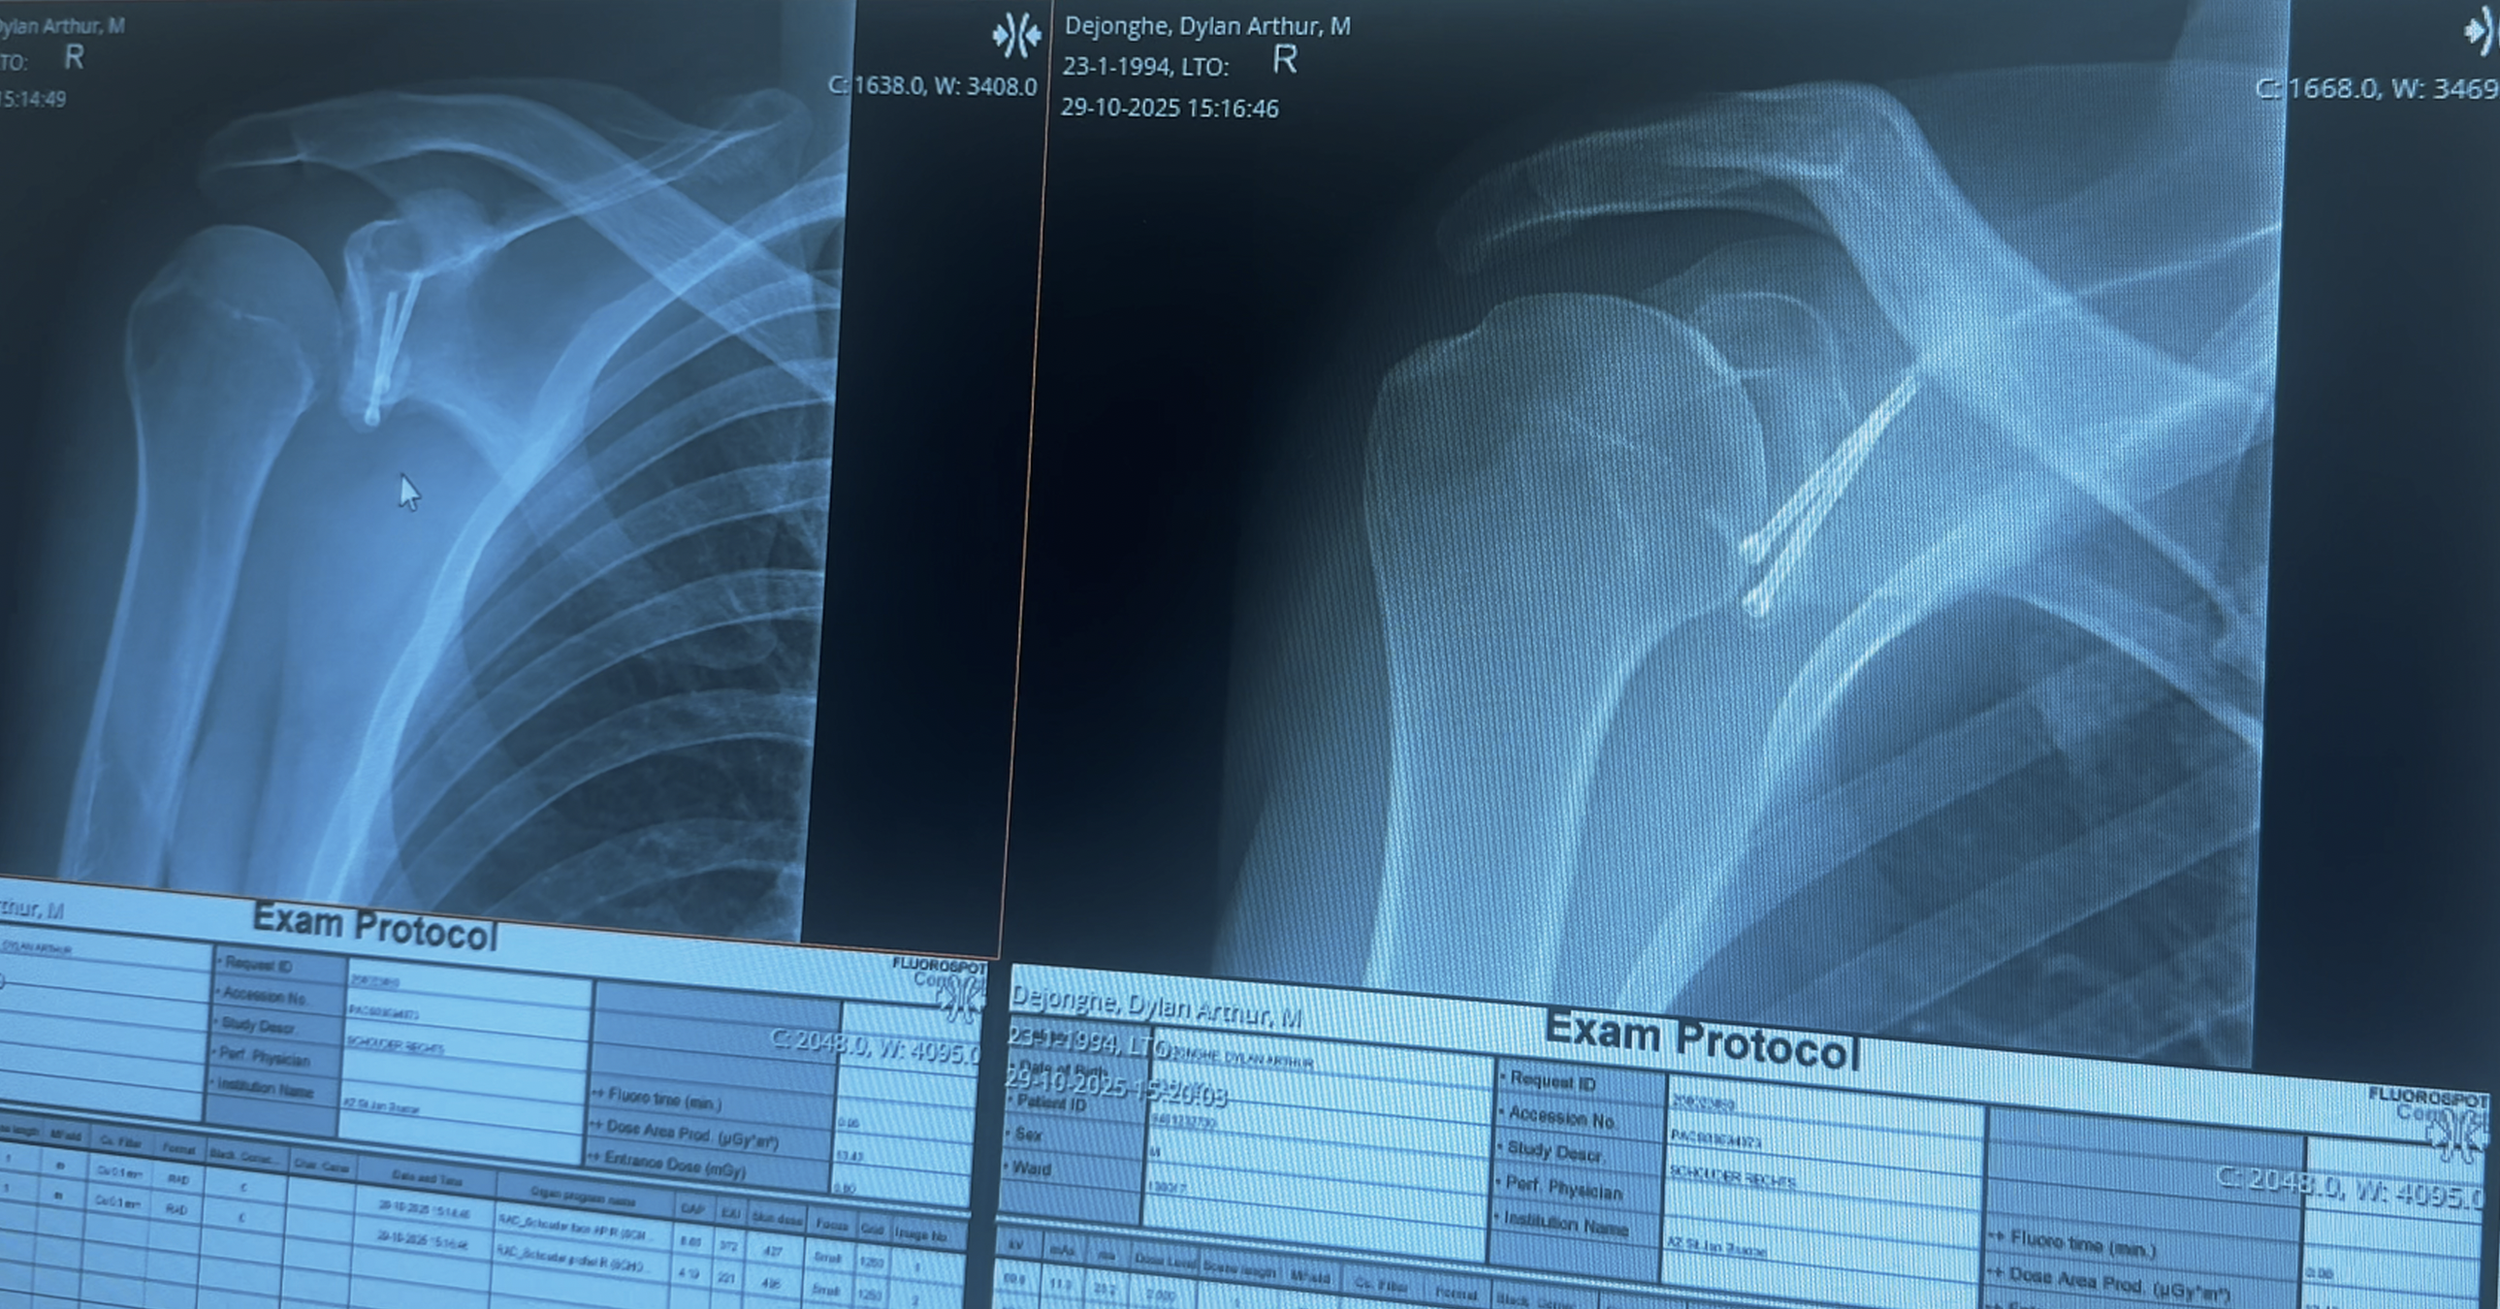

Enige tijd geleden onderging ik een Latarjet-procedure aan mijn schouder. Na meerdere subluxaties en ontwrichtingen in het verleden gaf mijn arts mij een duidelijke keuze: óf een operatie ondergaan, óf mijn sportactiviteiten sterk verminderen. Aangezien ik 31 ben en enorm gepassioneerd ben door sport, voelde de beslissing vrij vanzelfsprekend.

Veertien dagen pijn en zes maanden revalidatie, gevolgd door een volledige terugkeer naar training, leken een eerlijke ruil. De operatie zelf verliep goed en over het algemeen was de postoperatieve pijn goed te verdragen.

Ik kan mijn arm niet meer optillen, noch naar voren, noch zijwaarts. De huidige verdenking is aanzienlijke zenuwschade. Waarschijnlijk houdt dit verband met de injectie die ik vóór de operatie in mijn nek kreeg. In dat gebied bevindt zich een belangrijk zenuwknooppunt dat signalen naar de spieren stuurt. Er is een reële kans dat de anesthesioloog per ongeluk in dat gebied heeft geïnjecteerd, meer bepaald in de truncus superior.

Intussen heb ik MRI-onderzoeken ondergaan van mijn nek, schouders en armen. Het doel is om de exacte oorzaak van deze complicaties vast te stellen.